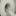

The world's first fully digital magnetic scanner . Suffice it to say that in a second measurement is recorded and processed one billion bits of data in real time. The use of the latest technological advances brought results: obtained image quality is not worse than on costly foreign imagers . Prices of the last times and reach 160 million rubles. The problem of high prices has become known throughout the country thanks to the president's robust language.

Take our scanner. Many also did not believe in creating it. There is no government funding we have received. But today the scanner already exists and has more than one hundred patients. It should be noted, we did not want to cry about this achievement until you went all the way from idea to put it into practice - that is, until real Clinical operating system. And what we see now? Image obtained by MRI scanner "Unitom", which should become the prototype of the Public MRI scanner, it is not worse than the images obtained by MRI promoted foreign production.

Just look at the captured images, and do all yourself. The problem is that many do not even want to believe your eyes, do not want to believe the facts. So, I talked to one doctor who considers himself a professional in the diagnosis. He did not even look at the pictures that I showed him. That's what worries, to put it mildly...